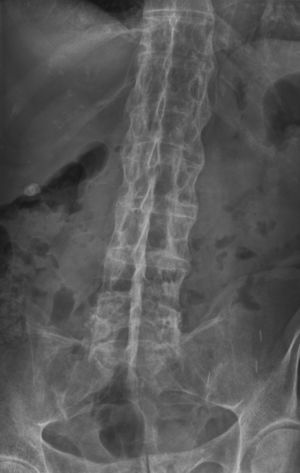

التهاب الفقار المقسط أو اللاصق Ankylosing spondylitis باليونانيةankylos, stiff; spondylos, vertebrae), تسمى قديماًBekhterev's disease, Bekhterev syndrome, و Marie-Strümpell disease هو نوع من التهاب المفصل في العمود الفقري. وهو يسبب تورماً بين الفقرات، والفقرات هي الأجزاء الأسطوانية التي تكون العمود الفقري، كما يسبب تورماً في المفاصل بين العمود الفقري والحوض. إن التهاب الفقار المقسط أو اللاصق هو أحد أمراض المناعة الذاتية. إن الجهاز المناعي المسؤول عن حماية الجسم من العدوى يقوم بمهاجمة أنسجة الجسم نفسها في حالة أمراض المناعة الذاتية. ويكون التهاب الفقار اللاصق أكثر انتشاراً وخطورة عند الرجال. وكثيراً ما يكون مرضاً ينتقل عن طريق الوراثة.[1]

ومن أعراضه المبكرة ألم الظهر والتيبس. وهي تبدأ غالباً في مرحلة المراهقة المتأخرة أو أوائل البلوغ. ومع مرور الوقت يمكن لالتهاب الفقار اللاصق أن يؤدي إلى التحام الفقرات مما يقيد حركتها. يمكن أن تتفاقم الأعراض كما يمكن أن تتراجع أو تختفي تماماً. إن هذا المرض غير قابل للشفاء، لكن الأدوية يمكن أن تهدئ الألم والتورم والأعراض الأخرى. ويمكن أن تكون التمارين الرياضية مفيدة أيضاً.

يبدأ التهاب الفقار المقسط في صغار البالغين بألم مبهم في أسفل الظهر، ويبوسة مديدة تالية للراحة تتحسن جزئياً بالحركة والتمارين الرياضية. ينتشر الألم إلى الاليتين والقسم الخلقي من الساقين. كما يحدث ألم في القفص الصدري بإصابة المفاصل الغضروفية المركزية فيه، وقد يكون لهذا الألم صفات جنبية، ويظهر الألم أيضاً في مفاصل قبضة القص Manubriosternal والمفاصل القصية الترقوية. إن التهاب ارتكازات الأربطة والأوتار عرض بارز وقد يكون العرض الأول. وينجم الألم عن التهاب الأصابع Dactylitis ' أو وتر أشيل، أو اللفافة الأخمصية، أو عرف الحرقفة iac أ I Crest. تكون الإصابة المفصلية بشكل الام مفصلية، أو التهاب مفاصل عديد، يصيب المفاصل الزليلة الدانية وبشكل غير متناظر كالكتفين والمرفقين والركبتين ونادرا المفاصل الصغيرة القاصية. وتترافق هذه الإصابة بيبوسة صباحية مديدة وأحياناً بتورم الا أنه من غير الشائع حدوث إصابة مفصلية تاكلية شديدة.

يحدث التهاب العنبية الأمامي في حوالي ربع المرضى، ويتظاهر بألم واحمرار وخوف من الضياء، وتكون هذه الإصابة نوبية، وحيدة أو ثنائية الجانب. يبدي الفحص السريري نقصاً في حركية العمود الفقري، مع فقد تام أو جزئي للقعس القطني الفيزبولوجي، وزيادة في الحدب الظهري. أما المظاهر المتأخرة فتشمل تحدد حركة جدار الصدر في الشهيق العميق (أقل من 2.5 سم) مع انحناء تدريجي، وثبات العمود الفقري والرأس في وضعية العطف. ويمشى المريض جاراً قدميه Shuffling Gait مع تفاوت شدة إصابة المفاصل المحيطة.[2]